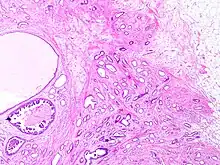

Tubular carcinoma is a subtype of invasive ductal carcinoma of the breast.[2][3] More rarely, tubular carcinomas may arise in the pancreas[4] or kidney.[5] Most tubular carcinomas begin in the milk duct of the breast and spread to healthy tissue around it.[6][7]

Tubular carcinomas are generally around 1 cm. or smaller, and are made up of tubules. They are usually low-grade.[2] Elastosis has been noted as common but is not present in all cases.[11]

A highly differentiated invasive carcinoma that forms well-defined tubules (containing epithelium, but no myoepithelium) and that have abundant desmoplastic fibrous stromal reaction between the tubules.